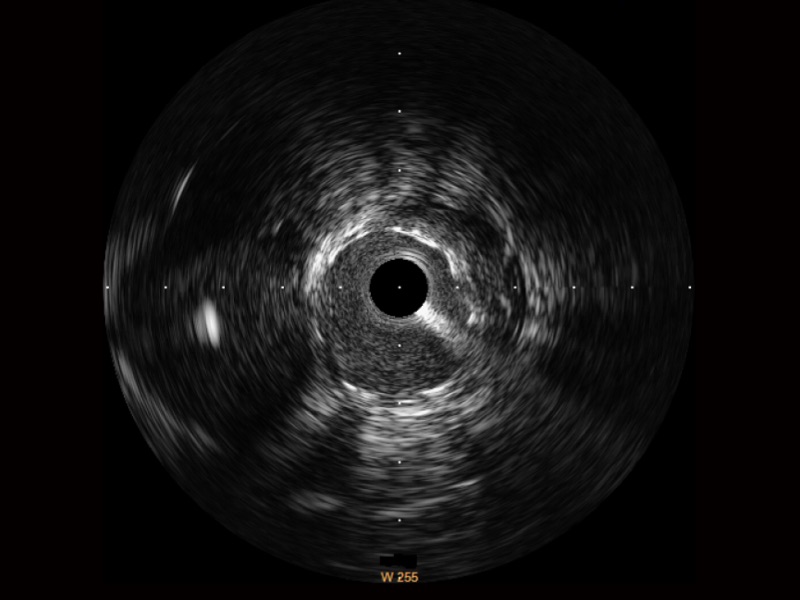

血管内超声(IVUS) 通过对病变程度、性质和累及范围的精确判断,可帮助选择治疗策略和方法,指导介入治疗过程,能够降低主要不良心血管事件,改善预后,在复杂病变介入治疗中用于指导支架置入的优势更为明显。血管内超声(IVUS)已成为精准心血管介入治疗的“金标准”。

环球UG官网始终关注未满足的临床需求:超宽频成像技术同时提供高清分辨力和充足穿透深度,适应不同血管结构的治疗引导;智慧赋能,简化操作,降低临床应用难度和缩短学习曲线。

宽频成像,兼具高分辨力和更大穿透深度